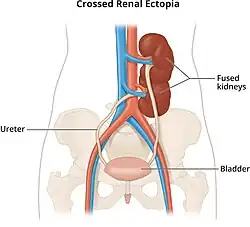

- Crossed: kidney that crosses the midline so that it's on the opposite side of the body. It can be with or without fusion to the ipsilateral kidney.[2]